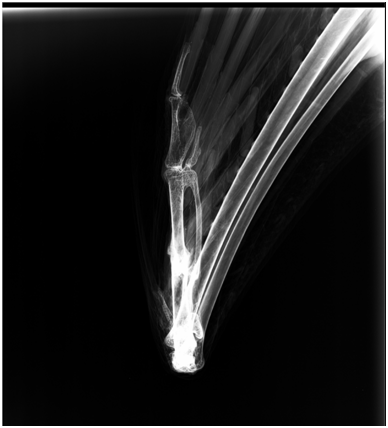

One rescued adult male lesser adjutant stork was received at Nandankanan Zoological Park, Odisha, India on 12.06.2011. The stork was housed in a caged enclosure of floor area 120 Sqm and provided with small fish 200g and two day old chicks daily as feed. On 10.03.2018, the said stork was observed with flexed right wing, dullness and anorexia. Upon physical examination of the right wing, the sharp edge of bone was found protruding outside breaching skin. Radiographic examination of the affected wing revealed compound fracture of right carpometacarpal bone at the mid shaft (Figure 1). The wound site was soiled and blood stained. The bird was weighed to be 5 Kg.

Figure 1 Radiograph image showing carpometacarpus fracture.